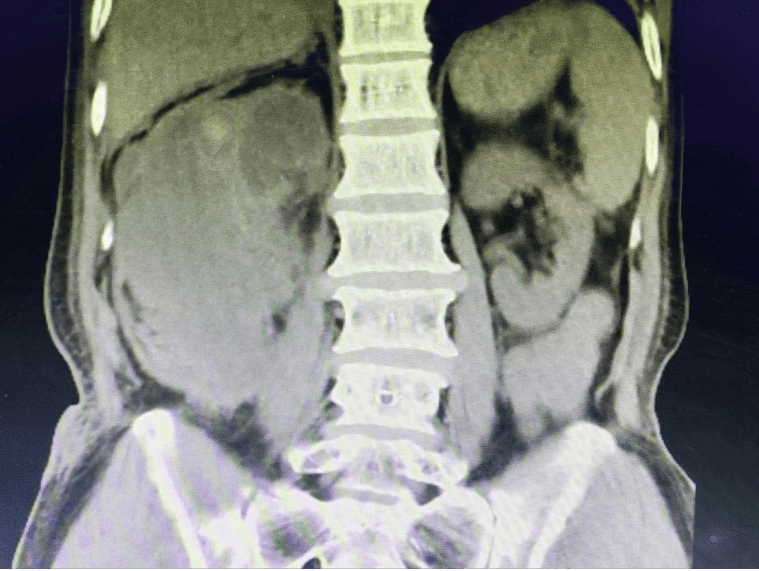

入院时CT片

经初步检查发现杨爷爷肾结石多发且引起右肾重度积水并出血,肾功能严重损害,合并有胸腔大量积液、心脏病、贫血等基础疾病,麻醉和手术风险极高。患者希望“既要治病,又要保肾。”为帮助杨爷爷解除多年疾病困扰,泌尿外科学科带头人罗洪星带领专家团队联合麻醉科、呼吸内科、ICU、心内科等多学科专家经过反复讨论和分析,结合患者诉求,最终为杨爷爷制定了个性化治疗方案。